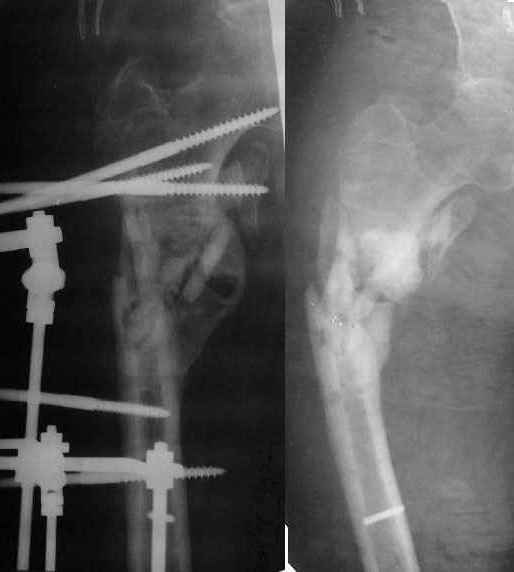

Неудачный остеосинтез пластиной: поломка винтов, миграция фиксатора. После удаления пластины сформировался гипопластический ложный сустав нижней трети бедренной кости, укорочение н/к 5 см. Выполнялся дистакционный остеосинтез аппратом Илизарова на штифте. Зона ложного сустава "не открывалась". Через 10 месяцев, когда даже регенерат полностью перестроился, консолидации в зоне ложного сустава не наступило, несмотря на стабильную фиксацию и постоянную компрессию(штифт+аппрата на 4 кольцах).